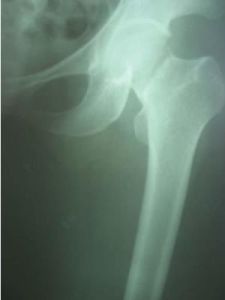

股骨骨折股骨幹骨折是人體中最長的管狀骨。股骨幹包括粗隆下2-5cm至股骨髁上2-5cm的骨幹。股骨幹為三組肌肉所包圍,其中伸肌群最大,由股神經支配;屈肌群次之,由坐骨神經支配;內收肌群最小,由閉孔神經支配。由於大腿的肌肉發達,骨折後多有錯位及重疊。股骨幹周圍的外展肌群,與其它肌群相比其肌力稍弱,外展肌群位於臀部附著在大粗隆上,由於內收肌的作用,骨折遠端常有向內收移位的傾向,已對位的骨折,常有向外弓的傾向,這種移位和成角傾向,在骨折治療中應注意糾正和防止。股骨下1/3骨折時,由於血管位於股骨折的後方,而且骨折遠斷端常向後成角,故易刺傷該處的膕動、靜脈。股骨幹骨折系指小粗隆下2-5厘米至股骨髁上2-5厘米的股骨骨折,占全身骨折的4-6%,男性多於女性,約2.8∶1。10歲以下兒童占多數,約為總數的1/2。

肱骨外科頸骨折 兒童的股骨幹骨折可能為不全或青枝骨折;成人股骨幹骨折後,內出血可達500-1000ml。可發生斜形、螺鏇形或青枝骨折。骨折發生的部位以股骨幹中下1/3交界處為最多,上1/3或下1/3次之。骨折端因受暴力作用的方向,肌群的收縮,下肢本身重力的牽拉和不適當的搬運與手法整復,可能發生各種不同的移位。股骨幹上1/3骨折時,骨折近段因受髂腰肌,臀中、小肌及外鏇肌的作用,而產生屈曲、外展及外鏇移位;遠骨折段則向後上、內移位。

股骨幹中1/3骨折時,骨折端移位,無一定規律性,視暴力方向而異,若骨折端尚有接觸而無重疊時,由於內收肌的作用,骨折向外成角。股骨幹下1/3骨折時,由於膝後方關節囊及腓腸肌的牽拉,骨折遠端多向後傾斜,有壓迫或損傷膕動、靜脈的危險,而骨折近端內收向前移位。

股骨上1/3骨折後,近折段受骼腰肌、臀中肌、臀小肌和髖關節外鏇諸肌的牽拉而屈曲、外鏇和外展,而遠近段則受內收肌的牽拉而向上、向後、向內移位,導致向外成角和縮短畸形。股骨中1/3骨折後,其畸形主要是按暴力的撞擊方向而成角,遠折段又因受內收肌的牽拉而向外成角。股骨下1/3骨折段受腓腸肌的牽拉而向後傾倒,遠側骨折端可壓迫或刺激膕動脈、膕靜脈和坐骨神經。